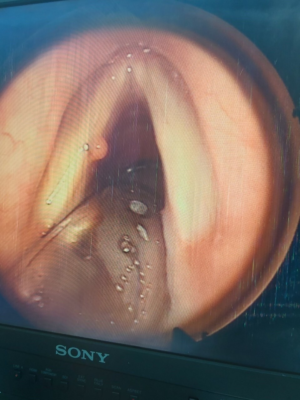

Hình 2: Polyp dây thanh (T)

Polyp dây thanh trái trước và sau phẫu thuật của bệnh nhân Nguyễn Thị T